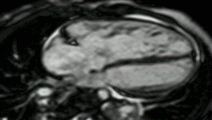

Infarct imaging using contrast

Scar is best seen after giving a contrast agent, typically one containing gadolinium bound to DTPA. With a special sequence, Inversion Recovery (IR) normal heart muscle appears dark, whilst areas of infarction appear bright white.

CMR in the 4 chamber view comparing the cine (left) with the late gadolinium image using inversion recovery (right). The subendocardial infarct is clearly seen. Fat around the heart also appears white.